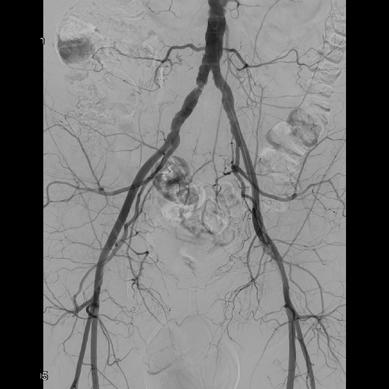

The focus of their study was to establish the role of IR in the management of potentially lifethreatening postpancreatectomy complications such as PPH, thus preventing re-exploration. To do so, Kulkarni and colleagues enrolled 758 patients who underwent pancreatic surgery between January 2014 and December 2019. All patients who developed post-surgical complications within 90 days of primary hospitalisation were included. Complications were classified according to the International Study Group of Pancreatic Surgery (ISGPS).

The types of surgery included in the study were pancreatectomy (4%), pancreaticoduodenectomy (73.8%), enucleation (1%), pancreatectomy and vein resection (4.85%), and multivisceral pancreatic surgery (16.5%). Of the 758 patients included, 206 (27.2%) developed post-surgical complications. Of these, 46 patients (6%) experienced PPH, with 30 patients (3.96%) requiring intervention; 13 patients (43.3%) underwent angioembolization, of whom five (38.46%) died due to causes unrelated to PPH, while 17 patients (56.7%) underwent surgical reexploration.

The authors note that the 90-day mortality rate in patients with PPH was 17.39%, which is comparable

with other studies in the literature. For patients who underwent primary angioembolization for PPH, the mortality rate was 38.46%—which is not statistically significant, they detail. The causes of death for these five patients included biliary sepsis with multiorgan dysfunction, myocardial infarction, hepatic decompensation, and major hepaticojejunostomy and pancreatojejunostomy leaks. Kulkarni and colleagues state that “although PPH may have been a contributing factor, the causes of death were not directly related to the condition”.

“These five patients who underwent re-exploration were beyond the scope of management by IR,” state Kulkarni and colleagues, who explain that mortality rates in patients with PPH “remain high despite aggressive intervention”. They do note, however, that these patients also tend to have associated complications and comorbidities which contribute to increased mortality and morbidity rates. They describe that common comorbidities among this patient population are diabetes, hypertension, hypothyroidism and coronary artery disease; 45 patients in their study cohort presented with one comorbidity and 47 with multiple.

Elsewhere in their results, the researchers observed intra-abdominal fluid collections in 173 (22.8%) patients, with 147 (85%) undergoing image-guided interventions and 23 (13.3%) undergoing surgical re-exploration. The 90-day mortality rate after percutaneous image-guided intervention was 6.12% and after primary surgical re-exploration was 21.7%.

Among other results, the authors identified that biliary complications occurred in 31 patients (4%), of which 18 (58%) underwent image-guided intervention and 11 (35.5%) underwent surgical re-exploration. The 90-day mortality rates were 27.78% and 35.5% in the IR and surgical groups, respectively. Further,

the incidence of pancreatic fistula was observed in 20% of patients, 91.8% of whom were prevented from undergoing surgical re-exploration by use of IR management. The 90-day mortality rate in patients who underwent percutaneous drainage was 2.7% and 30.3% in those who underwent primary surgical re-exploration.

“Image-guided interventions successfully prevented re-exploration in 61.5% of PPH cases, 88.9% of biliary complications, and 99.3% of intra-abdominal fluid collections,” state Kulkarni et al, emphasising the “pivotal role” IR plays in managing post-surgical complications.

“IR provides a minimally invasive alternative to surgical re-exploration, reducing recovery time and preventing morbidity associated with re-exploration,” say the authors. They highlight that “early recognition and prompt intervention” are key in patients with PPH, biliary leak and portal vein thrombosis, as these are conditions associated with high mortality and morbidity rates. However, in cases where surgical re-exploration is required, this is “often due to complications which are beyond the scope of percutaneous management”, Kulkarni et al point out.